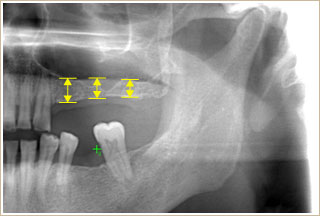

このようなレントゲン写真をご覧になられたことのある方は、多いかと存じます。

インプラントはレントゲンでこのように写ります。

通常歯科で撮影されるX線写真は、パノラマ法と呼ばれます。図の範囲を2次元的(平面)に写します。

左図で示すように顎顔面は、かなり複雑な解剖構造をしています。

この構造体を、1枚の平面写真でおさめるパノラマX線写真では、診断に限界があるのは明白です。

そこで、歯科においても医科と同様な、X線CT(コンピュータ断層撮影)検査による3次元の画像診断方法を取り入れるようになりました。

CT写真がインプラント治療の安全にどのように関わっているのか、具体例を提示します。